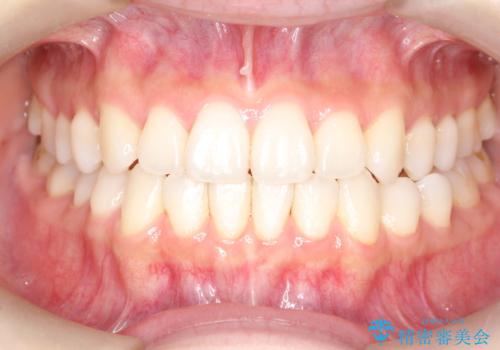

軽度の前歯のガタガタをインビザラインでの目立たない矯正

- 前歯のガタガタを主訴に来院されました。

軽度であったため、枚数制限のあるタイプのインビザラインのプランで治療することとしました。

軽度のガタガタを目立たずに手軽に矯正できるのもマウスピース矯正の魅力といえます。